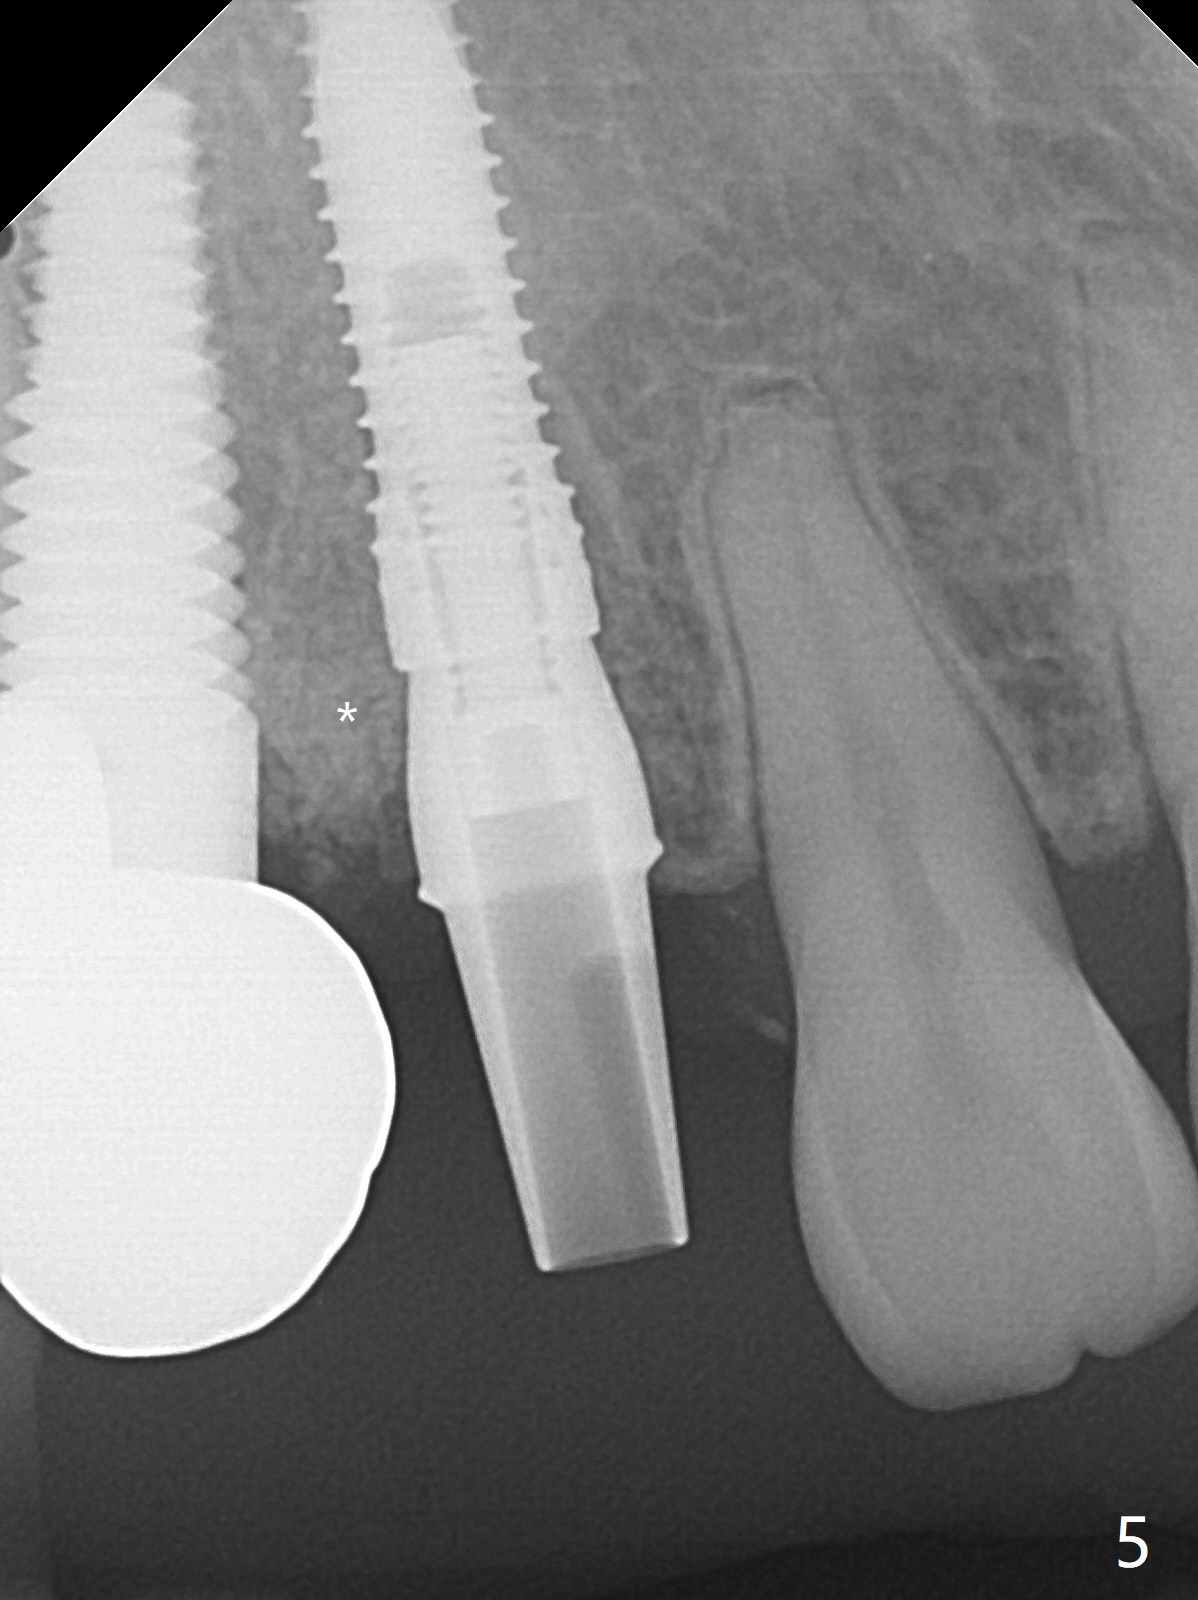

When the recemented crown at #6 is removed, the post is found to have been fractured. When the tooth is extracted, the socket walls are found intact. After moving the initial osteotomy (Fig.1) mesial, a 3.8x13 mm implant is placed (Fig.2). Clinically it appears supracrestal lingually. So the implant is placed deeper, but a cemented abutment is incompletely seated (Fig.3 <). When a longer abutment is used (easy grasping), it is seated completely (Fig.4). Then sticky bone is packed (Fig.5 *). When an immediate provisional is fabricated and seated, PRF membranes are inserted into the remaining gap between the gingiva and the provisional. Free hand surgery takes time and more intraop X-ray. It is inconvenient with nervous patients. The socket heals 2 weeks postop (Fig.6). The provisional will be next relined and reseated. It is difficult to insert gingival retraction cord 3.5 months postop because of the deep mesial margin. When an abutment with longer cuff is placed, the packing is easier (no biologic width violation, Fig.7 (^: resorbed mesial crest), as compared to Fig.5). When the crown is cemented (un-esthetic due to failure of use of temporary abutment), the metal shows at #5 with gingival recession because of buccal placement (Fig.8-10). Bone resorption is severe between #5 and 6 (Fig.7), as related to large gingival embrasure (Fig.9 *). When #5 crow is redone, move the gingival margin apical and fabricate provisional.